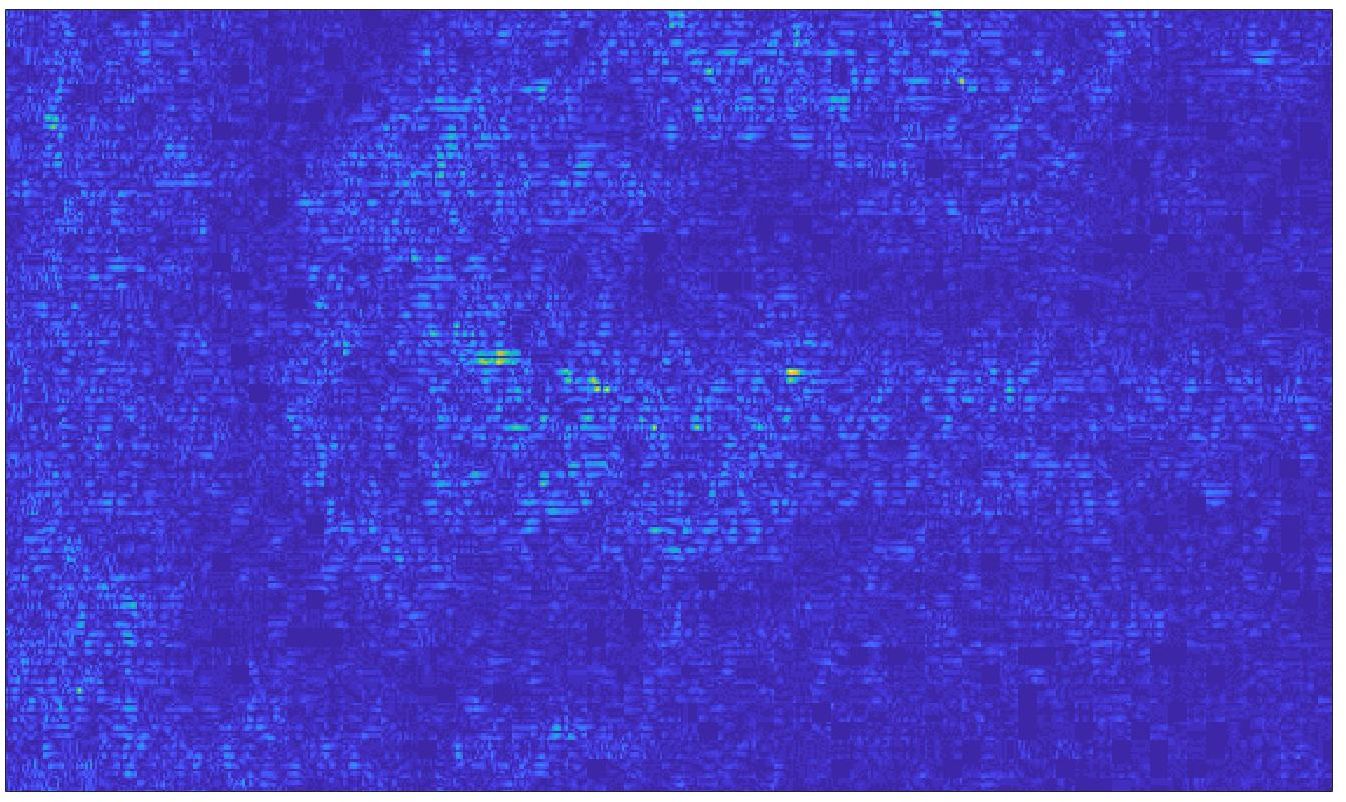

Our framework visually improves the results, in terms of blurring and artefacts. This result is more evident in the magnification of the ear of the foetus (Fig. 3), the mitral valve (Fig. 4), and the mass edges (Fig. 5). Fig. 6 shows the error image of the three anatomical districts with both 2X and 4X up-sampling factors, with the maximum error in the scale . The error is more evident in the contours of the anatomical structures; moreover, the abdominal district shows a smaller error than the cardiac and obstetric ones. We underline that the view for each image is scaled to its maximum, to improve the visualisation of the error.

The analysis of the absolute value of the difference between the input and the prediction of the network (Fig. 9) shows that the alteration of our prediction to the pixel values ranges from 0 to a maximum absolute value of 20, mainly located on the edges of the anatomical structures; furthermore, the black uniform areas are less affected by the prediction. In terms of the distance between the input and the prediction, we do not observe a significant difference among anatomical districts and between 2X and 4X up-sampling.